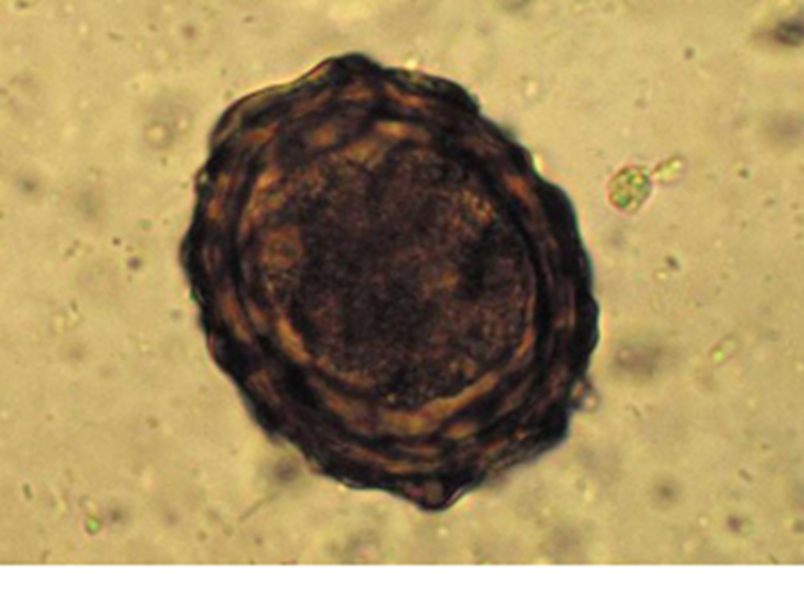

The eggs are virtually indestructable and can survive in the ground for many years, covered by a sticky coating (fig 5).

Fig 5: A. suum egg shed in faeces**

Immunity to adult worms can develop but a sow may live in balance with the parasite - harbouring no more than a handful of adult worms that are all a rich source of eggs.

Milk spot lesions are temporary, resolving in 6-8 weeks and tend to peak in incidence in late summer/autumn, as the warmth of summer favours acceleration of the life cycle.

In many cases there will be no clinical sign of Ascaris infection until the burden of infection becomes high. Slower growth, weight loss and poor feed utilisation will occur but in extreme cases jaundice and liver failure can occur, and coughing may be a feature in young pigs in those recently infected as migration of larvae through the lungs progresses. In very heavy infections with matured worms, blockage of the gut and death can occur, particularly in growing pigs.(Fig 6)